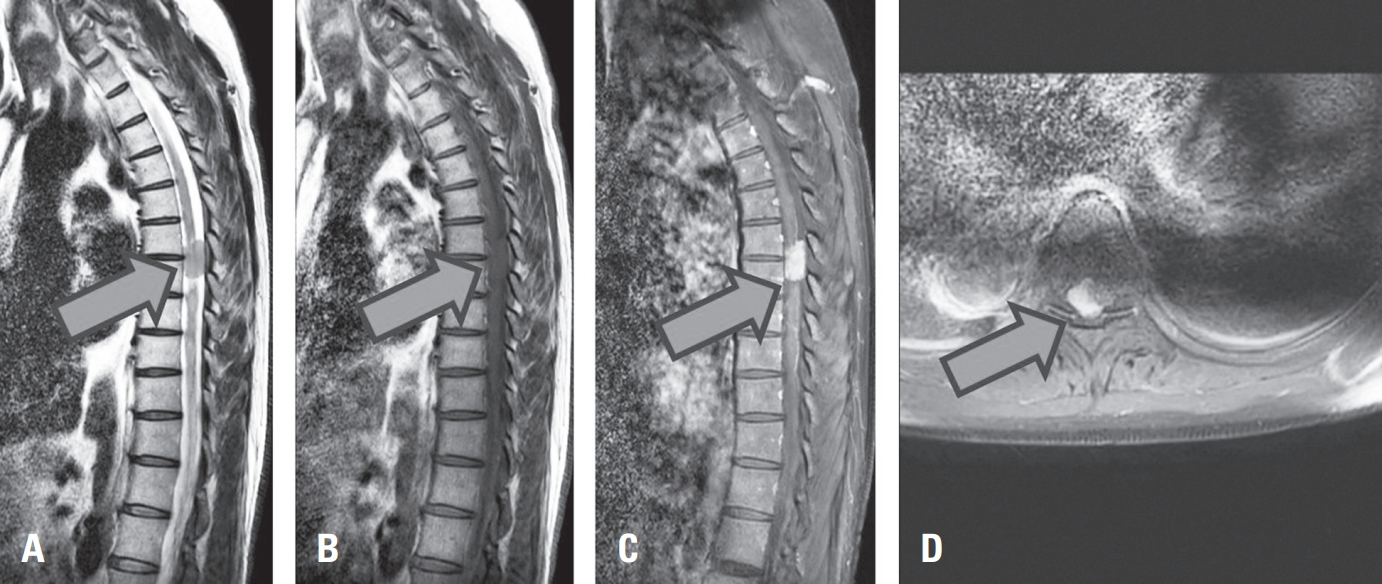

Spine-Shortening Osteotomy for Recurrent Adult Tethered Cord Syndrome Exacerbated by Traumatic Kyphosis: A Case Report

Tethered cord syndrome (TCS) is a condition in which the spinal cord becomes pathologically stretched due to various congenital or acquired etiologies, leading to progressive neurological symptoms. While surgical detethering is the gold standard for pediatric patients, adult-onset recurrent TCS presents a significant surgical challenge. Reoperation carries substantial risks—including spinal cord injury, cerebrospinal fluid leakage, and a high rate of retethering—often resulting in suboptimal long-term outcomes. Recently, spine-shortening osteotomy (SSO) has emerged as an alternative technique to reduce spinal cord tension without direct manipulation of the neural elements. Here, we report a case of recurrent adult TCS associated with a lipomyelomeningocele, which was exacerbated by post-traumatic kyphosis from an L1 compression fracture. The patient was successfully treated with SSO at the L1 level. This case highlights the utility of SSO as a safe and effective alternative to conventional revision detethering, particularly in complex cases involving spinal deformity.